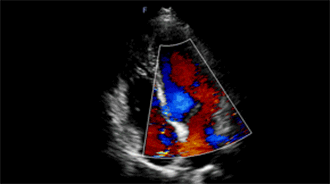

适用于成人心脏

频率高于传统心脏探头,更适用于婴幼儿心脏